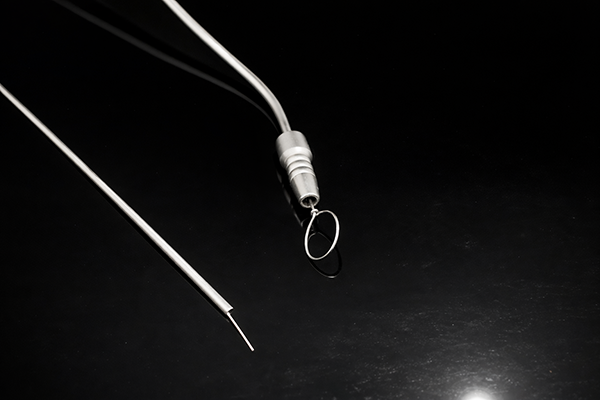

- Laparoscopy Instruments

- General Instrument

- Neuro Instrument

- Gyane Instrument

- Ent Instrument

- Orthopaedic Instrument